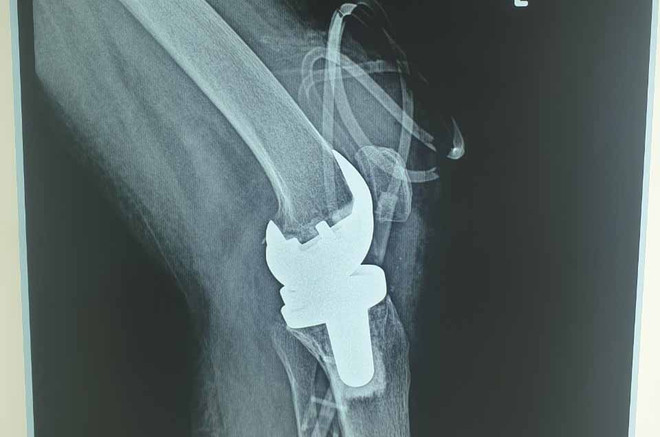

Lần đầu tiên bác sỹ Việt Nam thay khớp gối nhân tạo cho người mắc lao ảnh 1Phim chụp của bệnh nhân. (Ảnh: PV/Vietnam+)

Tháng 3/2021, bà Th. nhập viện theo lịch hẹn khám lại. Sau khi thăm khám và thực hiện các xét nghiệm thấy tình trạng viêm giảm nhiều, chụp phim đánh giá không còn áp xe khớp gối, các bác sỹ khoa Ngoại tổng hợp, bệnh viện Phổi Trung ương quyết định phẫu thuật thay khớp gối nhằm giúp cho người bệnh có cơ hội trở lại sinh hoạt bình thường.